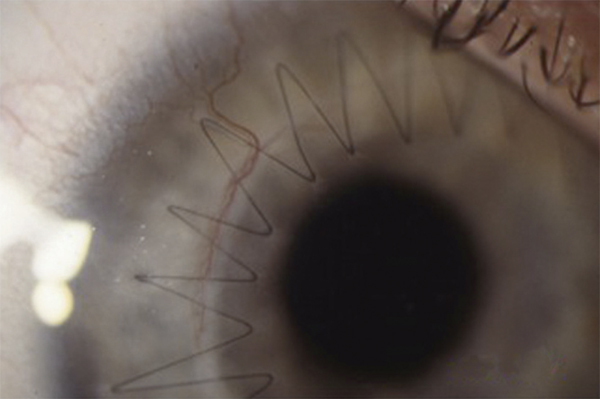

L’échec de la chirurgie filtrante du glaucome, quelle que soit la technique utilisée (trabéculectomie perforante ou non), est dans la majorité des cas la résultante d’une cicatrisation conjonctivale excessive au niveau de la bulle de filtration dans les mois suivant la chirurgie. Cela se caractérise par une prolifération fibroblastique anormale et une inflammation conjonctivale accrue associées à une fibrose excessive qui vient bloquer la sortie d’humeur aqueuse au niveau de l’espace sous-conjonctival. Aux classiques facteurs de risque de fibrose – patients mélanodermes, contexte inflammatoire, jeune âge, reprise chirurgicale, etc. – vient s’ajouter l’inflammation préopératoire conjonctivale, conséquence d’un traitement au long cours par les collyres antiglaucomateux [19, 20]. Broadway et al., notamment, ont montré une relation significative entre le risque d’échec de la chirurgie et le nombre de collyres utilisés d’une part, et la durée du traitement d’autre part [19]. Cela a fait l’objet, pendant la même période et par la suite, à la fois d’études histopathologiques sur des biopsies ou empreintes conjonctivales (fig. 12-6 et 12-7), et d’études cliniques prospectives ou observationnelles qui ont incriminé notamment les conservateurs. Ce n’est que récemment que le rôle supposé des conservateurs a été confirmé avec la démonstration épidémiologique d’un lien entre le taux d’échec et le nombre de collyres contenant du chlorure de benzalkonium (BAK) utilisés avant la chirurgie [21].

Fig. 12-6 Empreinte conjonctivale montrant une densité anormale en cellules inflammatoires chez un glaucomateux.

Fig. 12-7 Aspect similaire dans les différentes couches de la conjonctive sur une biopsie conjonctivale prélevée au moment de la chirurgie filtrante.